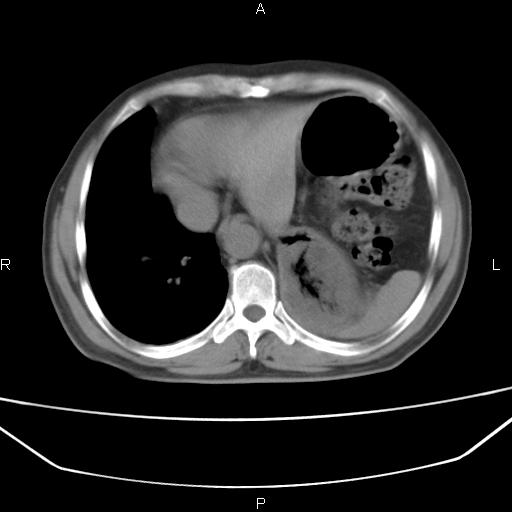

患者,男。50岁。近几日有咳嗽症状,无其他不适,既往病史无,考虑膈疝。请前辈们看看指导指导。

膈膨升,左下肺通气不良,膈肌好像还完整。

考虑左侧膈疝。

左侧膈疝。

符合隔膨升,膈肌较完整。